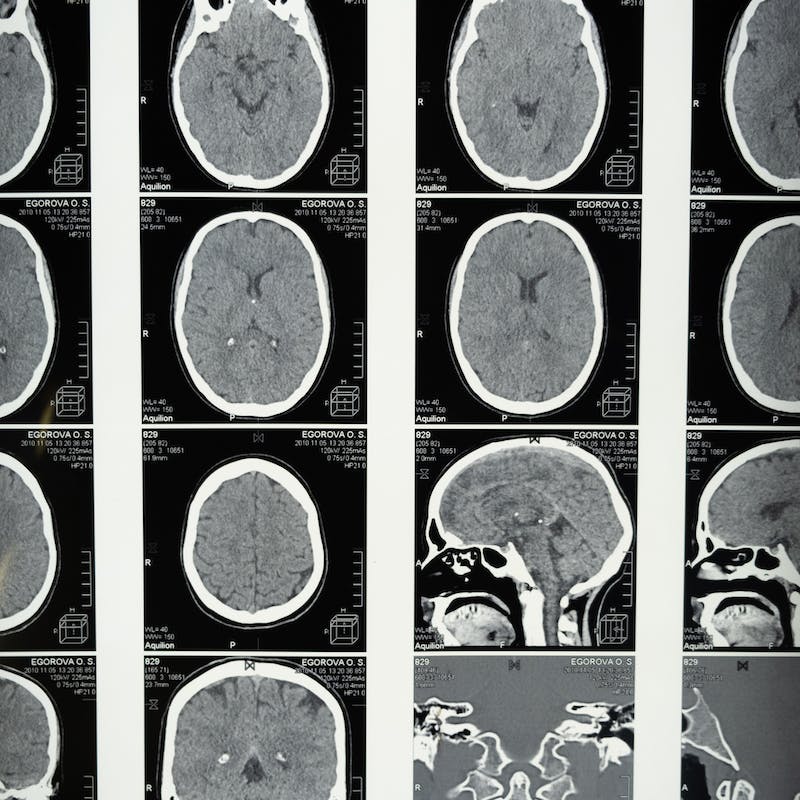

RESONANCIA DE CEREBRO

Sirve para obtener imágenes detalladas del cerebro y el tronco encefálico. Permite diagnosticar malformaciones, inflamación, sangrado, accidente cerebrovascular (ACV) y otras patologías cerebrales.

Requiere prescripción Cita en 24-48 h

Precio desde: 99€